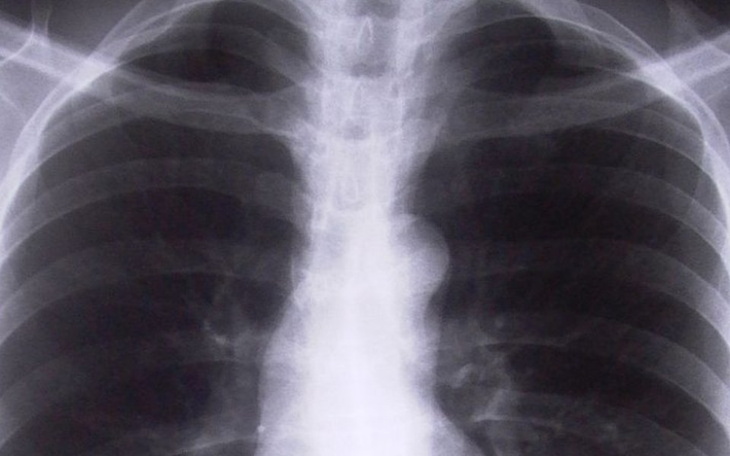

Moja chrzestna Kasia - najważniejsza osoba w moim życiu, która pomogła mi kiedyś spełnić największe marzenie i mimo swojej choroby, na którą zachorowała w 2013 roku zawsze mogłam liczyć teraz potrzebuje mojej pomocy. Zaczęło się od nowotworu nerki,pozniej kolejno lekarze stwierdzali przerzuty na płuca,piersi, szyje i głowę. Od tego roku łącznie ciocia przeszła 9 operacji i naprawdę liczne radioterapie oraz chemioterapie.

Najgorszy natomiast jest ten rok...ponieważ okazało się, że guz jest szybszy i operacje oraz chemioterapia zatrzymują go tylko na chwilę, a NFZ innego leczenia nie refunduje.

Mianowicie po ostatnich badaniach okazało się, że jest mozliwość podania jej Erbitux'u (lek na nowotwór głowy i szyi) oraz Nivolumab'u (Obdivo) na raka płuc i nerki. Leki te w Polsce nie są refundowane, a tylko to może pomóc mojej cioci powstrzymać dalszy rozrost guza jak i zmniejszyć go.

Leki mają być podawane jeszcze przez pół roku, miesięczny koszt Obdivo to około 23 tys zł, a Erbitux'u około 12 tys zł co daje sumę ponad 200 tys zł do tego dochodzi koszt odżywek, osłonowych leków oraz częstych dojazdów do szpitala, ponieważ leki mogą być podawane tylko pod nadzorem lekarza doświadczonego w stosowaniu leków przeciwnowotworowych, który po zakończeniu podawania leku musi kontrolować stan cioci jeszcze przez co najmniej godzinę.

Sytuacja jest na tyle poważna,że ciocia kilka dni temu trafiła do szpitala z powodu braku kontynuacji leczenia, a lekarze po kilku dniach - dokładnie 10.10.2019 r. po prostu ją wypisali i nie dają jej większych szans bez tych leków.